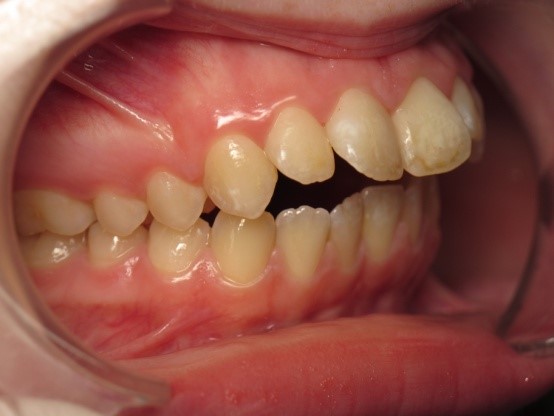

Pic.22. Tortoocclusion of teeth 11 and 21, open bite.

Pic.23. Tortoocclusion of teeth 11 and 21, prognathic, cross bite.